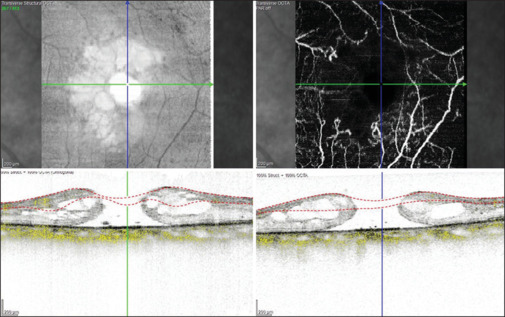

Purpose: This study aims to correlate optical coherence tomography angiography (OCTA)-based retinal microvasculature changes in cases of full-thickness macular hole (FTMH) before and after vitreoretinal surgery and its relation to patient's visual recovery.

Methods: Data of 31 eyes with FTMH were evaluated preoperatively and post-operatively at 6, 12, and 24 weeks for OCTA parameters and compared.

Results: 93.55% eyes (29 eyes) showed improvement in best-corrected visual acuity at 24 weeks. The mean foveal avascular zone (FAZ) significantly reduced from 0.41 ± 0.13 mm2 (preoperatively) to 0.25 ± 0.01 mm2 (postoperatively at 24 weeks). Mean preoperative vessel density (VD) in the superficial vascular plexus (SVP) progressively improved to 24.2% ± 2.2%, 25.2% ± 2.1% and 25.8% ± 2.3% at 6, 12, and 24 weeks respectively from 24.4% ± 2.1% preoperatively (P = 0.0, F = 5.1). The mean VD of foveal region in the SVP significantly improved (P < 0.0, F = 13.9) while that of the parafoveal region did not improve at 24 weeks (P = 0.3, F = 1.2) when compared with its preoperative status. The mean preoperative VD in the deep vascular plexus (DVP) was 20.2% ± 2.6%. It significantly improved at 6, 12, and 24 weeks (20.3% ± 2.4%, 21.8% ± 2.3% and 22.1% ± 2.2%, respectively; P = 0.0, F = 6.9). The mean VD of foveal region and parafoveal region in the DVP showed significant improvement when compared with its preoperative status (P < 0.0, F = 39.3, P < 0.0, F = 13.7).

Conclusion: This study showed reduction in mean FAZ area and improvement in mean VD at SVP and DVP in the macula postoperatively. Routine perioperative OCTA-based documentation of macular vascularity in FTMH may throw a light in cases with anatomico-functional postoperative disparities in future.

Abstract Image